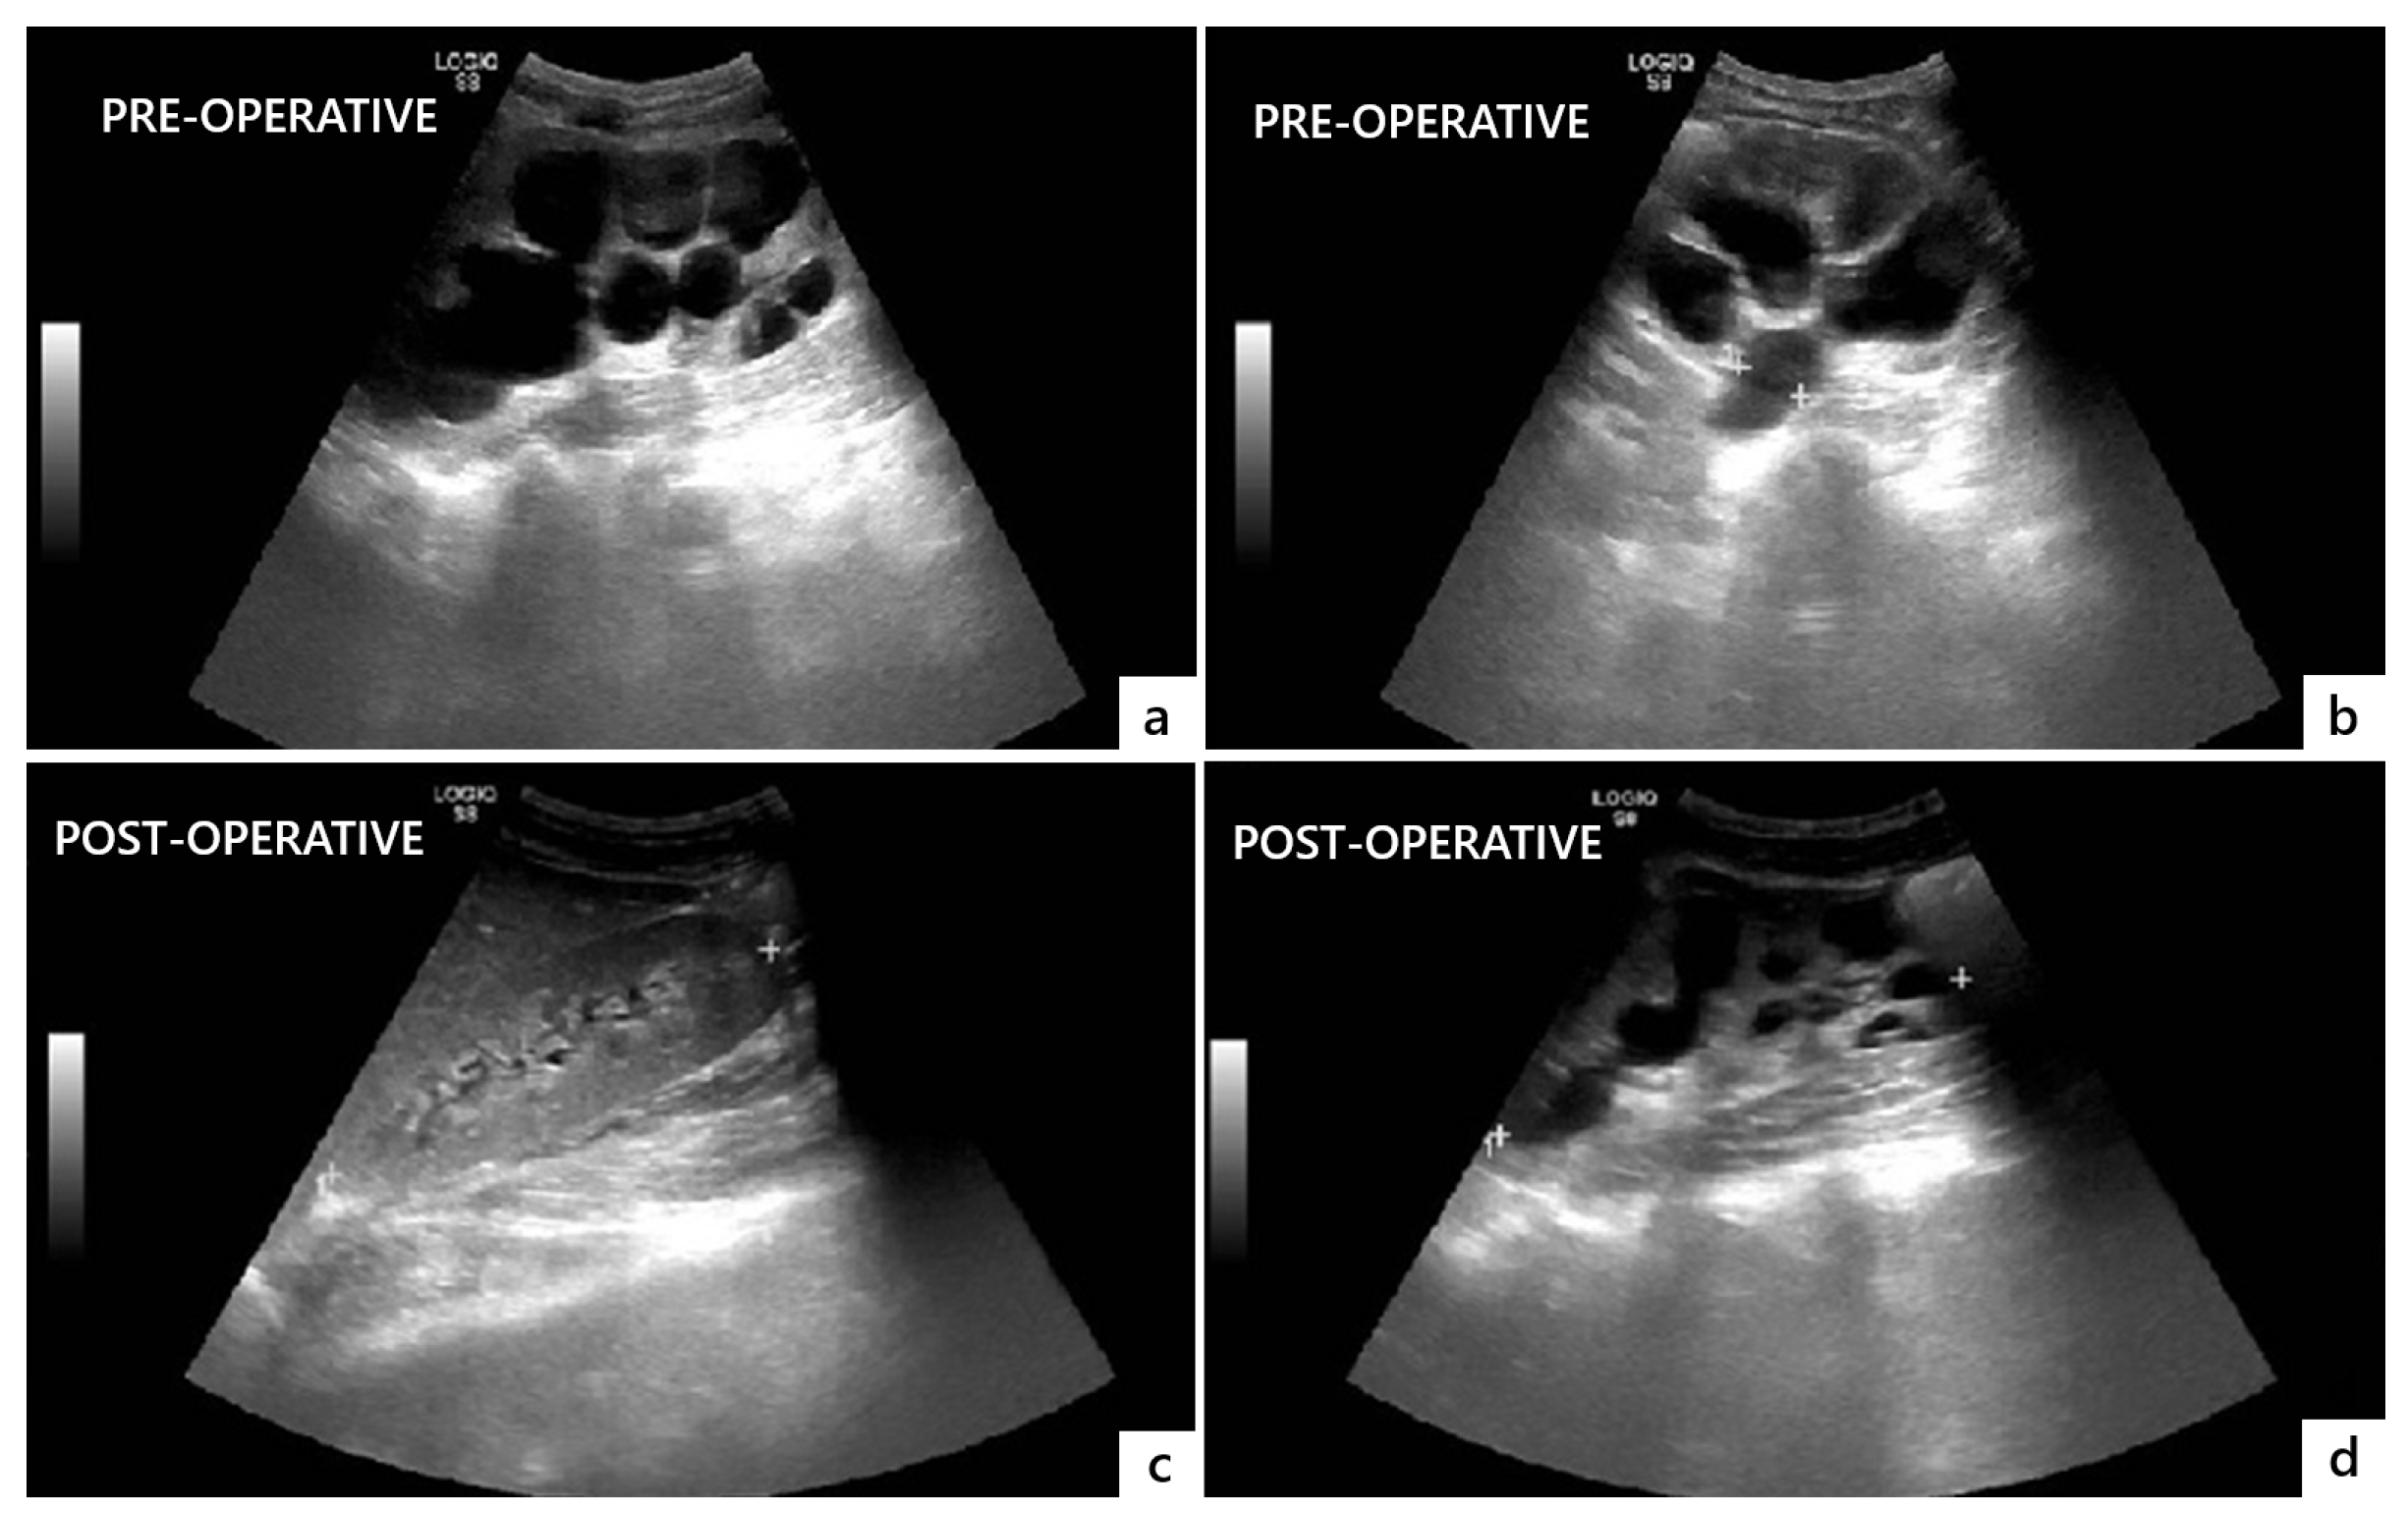

The postoperative course was uneventful, and the patient was discharged on postoperative day 14. He was instructed to regularly void at 3 h intervals and measure the PVR through the suprapubic catheter after each micturition. Postoperative US showed a significant decrease in bilateral hydroureteronephrosis and no significant PVR (Figure 4).

Figure 4.

Comparison of preoperative (a,b) and postoperative (c,d) ultrasonographic findings showing resolution of bilateral hydronephrosis and megaureter three months after surgery.

After surgery, renal function normalized (creatinine = 0.9 mg/dL), and a renogram demonstrated improved left renal drainage with T½ < 10 min and split renal function = 41%. Uroflowmetry at 3 months showed a maximum flow rate = 22.5 mL/s with a PVR < 50 mL, confirming functional recovery. The suprapubic catheter was removed three months after surgery.